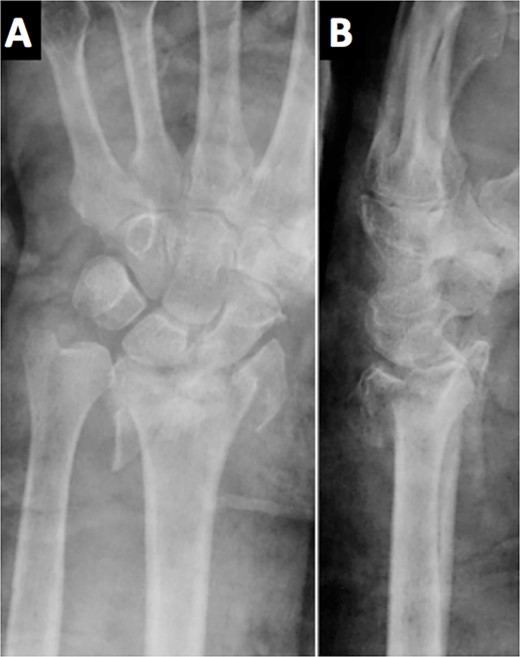

Due to the comminuted fracture and the bone osteoporosis, the final decision was closed reduction and fixation with K-wires. Due to the inadequate reduction, we decided to associate an external fixator. However, during surgery, an inadequate reduction of the ulnar column was observed, and thus, a mixed synthesis with an L-shaped plate was added (Fig. 2).